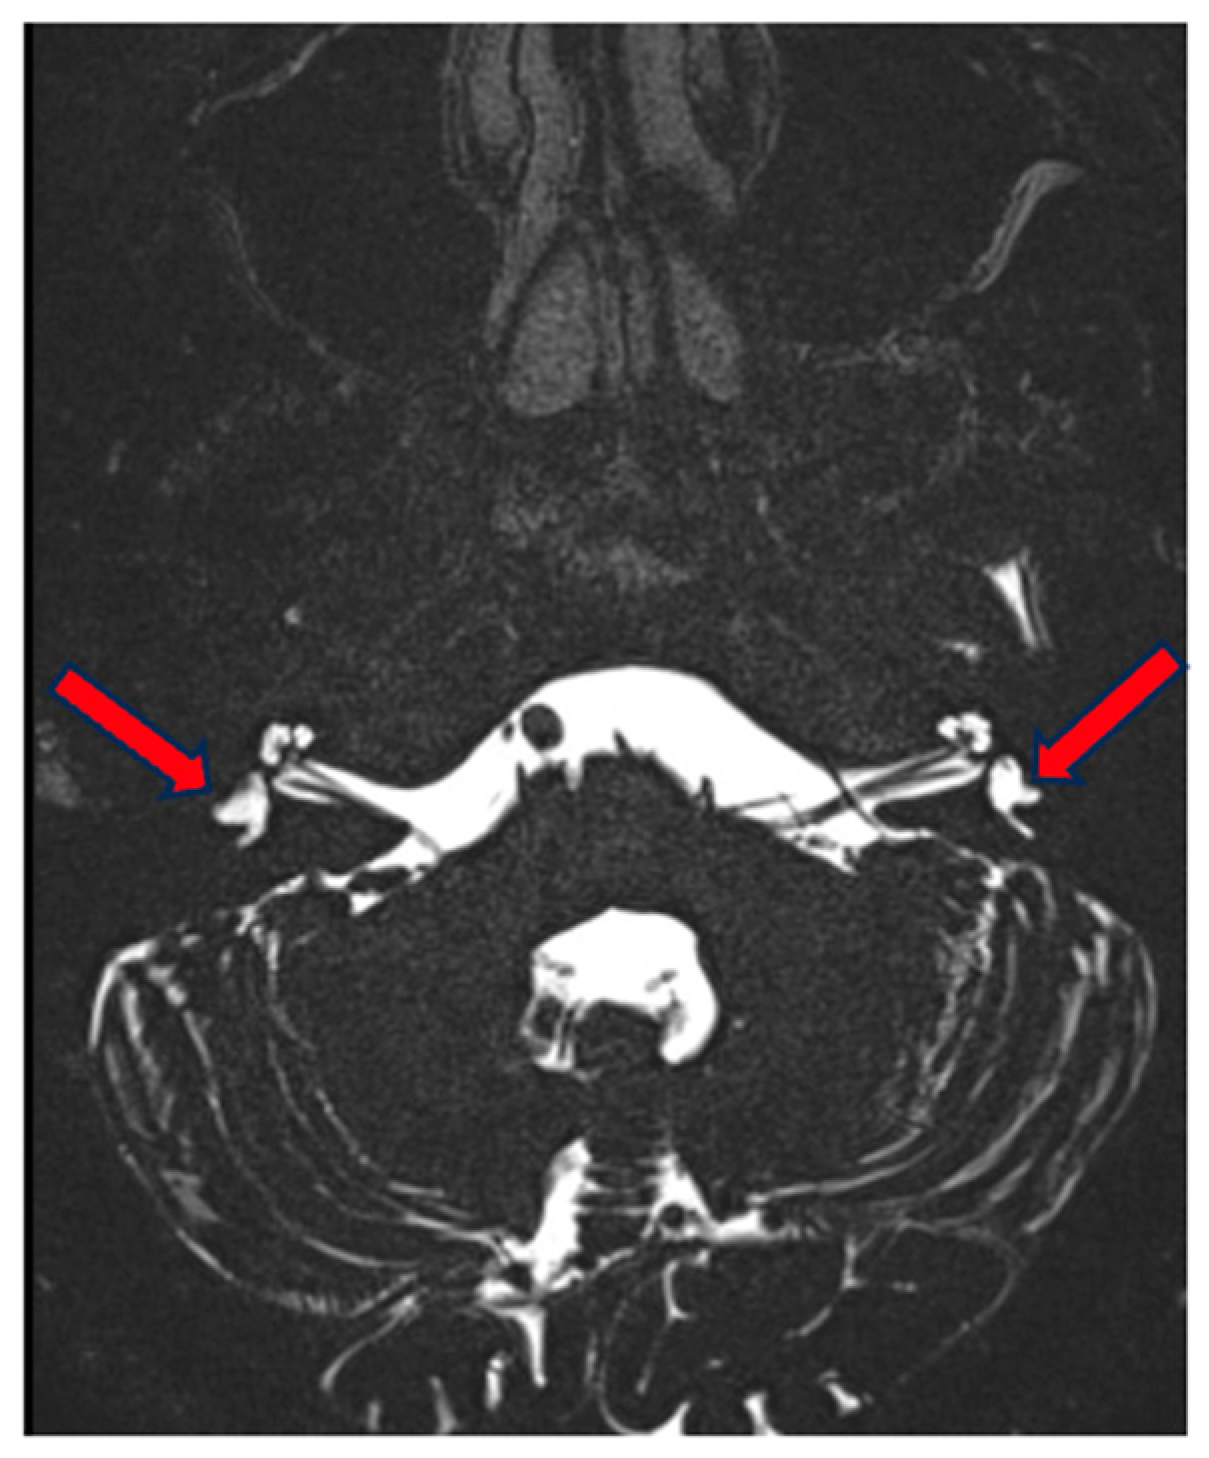

On MRI, we observed a correlating image with a normal aspect of the cochlea and vestibulum. On the right side, there is a normally formed superior semicircular canal but hypoplasia of the lateral semicircular canal, which is small and blunt, without a bony island. The posterior semicircular canal is small but forms a complete ring.

On the left side, the superior semicircular canal is only partially formed [only a posterior part] and not a complete ring. The lateral semicircular canal is hypoplastic, only partially formed posteriorly and blunt. The posterior semicircular canal is also relatively small [larger than on the right] but forms a complete ring (Figure 7). There was also an incidental finding of hypoplasia of the right facial nerve, which was radiologically not demonstrable in the internal auditory canal or internal auditory meatus, without clinical correlation.

Figure 7.

MRI of the inner ear for case 3, T2 tse3d weighted image, hypo-/dysplastic lateral semicircular canals bilaterally (red arrows).